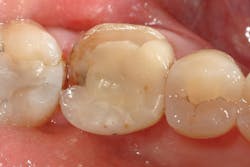

A 34-year-old female patient presented for previously planned treatment of full-coverage restorations on teeth Nos. 4, 5, 28, and 29. All four teeth were prepared according to reduction guidelines for Celtra Duo, scanned with a CEREC Omnicam, and milled with an MC-XL mill.

After milling, the restorations were adjusted intraorally for fit, occlusion, and esthetics. To increase workflow efficiency, especially in the premolar region, the crowns were not fired and were simply polished chairside using the CERECdoctors.com Finishing Kit (Meisinger).

Lastly, the intaglio of the crowns was treated with hydrofluoric acid and silane as described above, and definitive cementation was accomplished using Prime&Bond Elect and Calibra Ceram. Final occlusion and interproximal contacts were checked, and the patient was released after receiving four individual crown restorations all completed in one visit (figures 6 and 7).

Figure 6: Final Celtra Duo restorations on teeth Nos. 4, 5, 28, 29 on 34-year-old female patient.